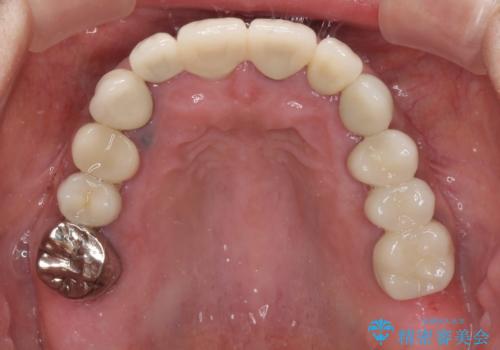

汚れてしまった前歯の仮歯 オールセラミッククラウンにて自然に

- 治療途中で装着していた仮歯汚れてしまい、恥ずかしいとのことで来院された患者様です。

土台の金属色が透けて見えてしまうため、ファイバーコアに置き換えた上で、オールセラミッククラウンにて補綴することとしました。

長い間億劫で手を付けていなかったものの、仮歯にした時点から自然な口元となり、視線が気にならなくなったとのことでした。

出来上がってきたセラミッククラウンはまるで自身の歯のようで、患者様には大変満足していただきました。